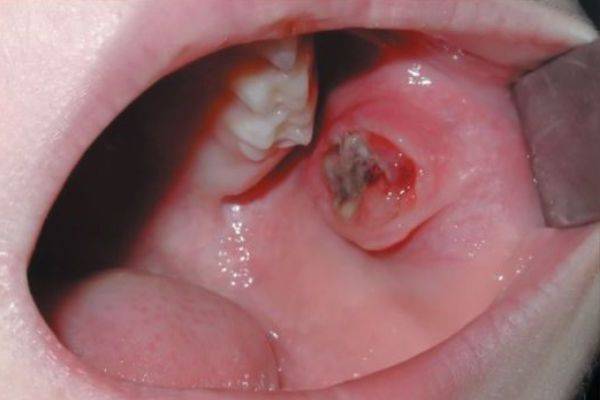

Кровь, поступающая из желудка, более темная, кашель сопровождается рвотными позывами и болью в животе, вместе с мокротой выделяются частицы пищи и другого желудочного содержимого. Диагностировать заболевания ротовой полости или носоглотки помогает обследование у стоматолога и ЛОР-врача.

- Трахеит, ларингит, тонзиллит – при этих заболеваниях у больных наблюдаются боль в горле, изменение голоса и кашель со скудной мокротой и небольшим количеством крови.